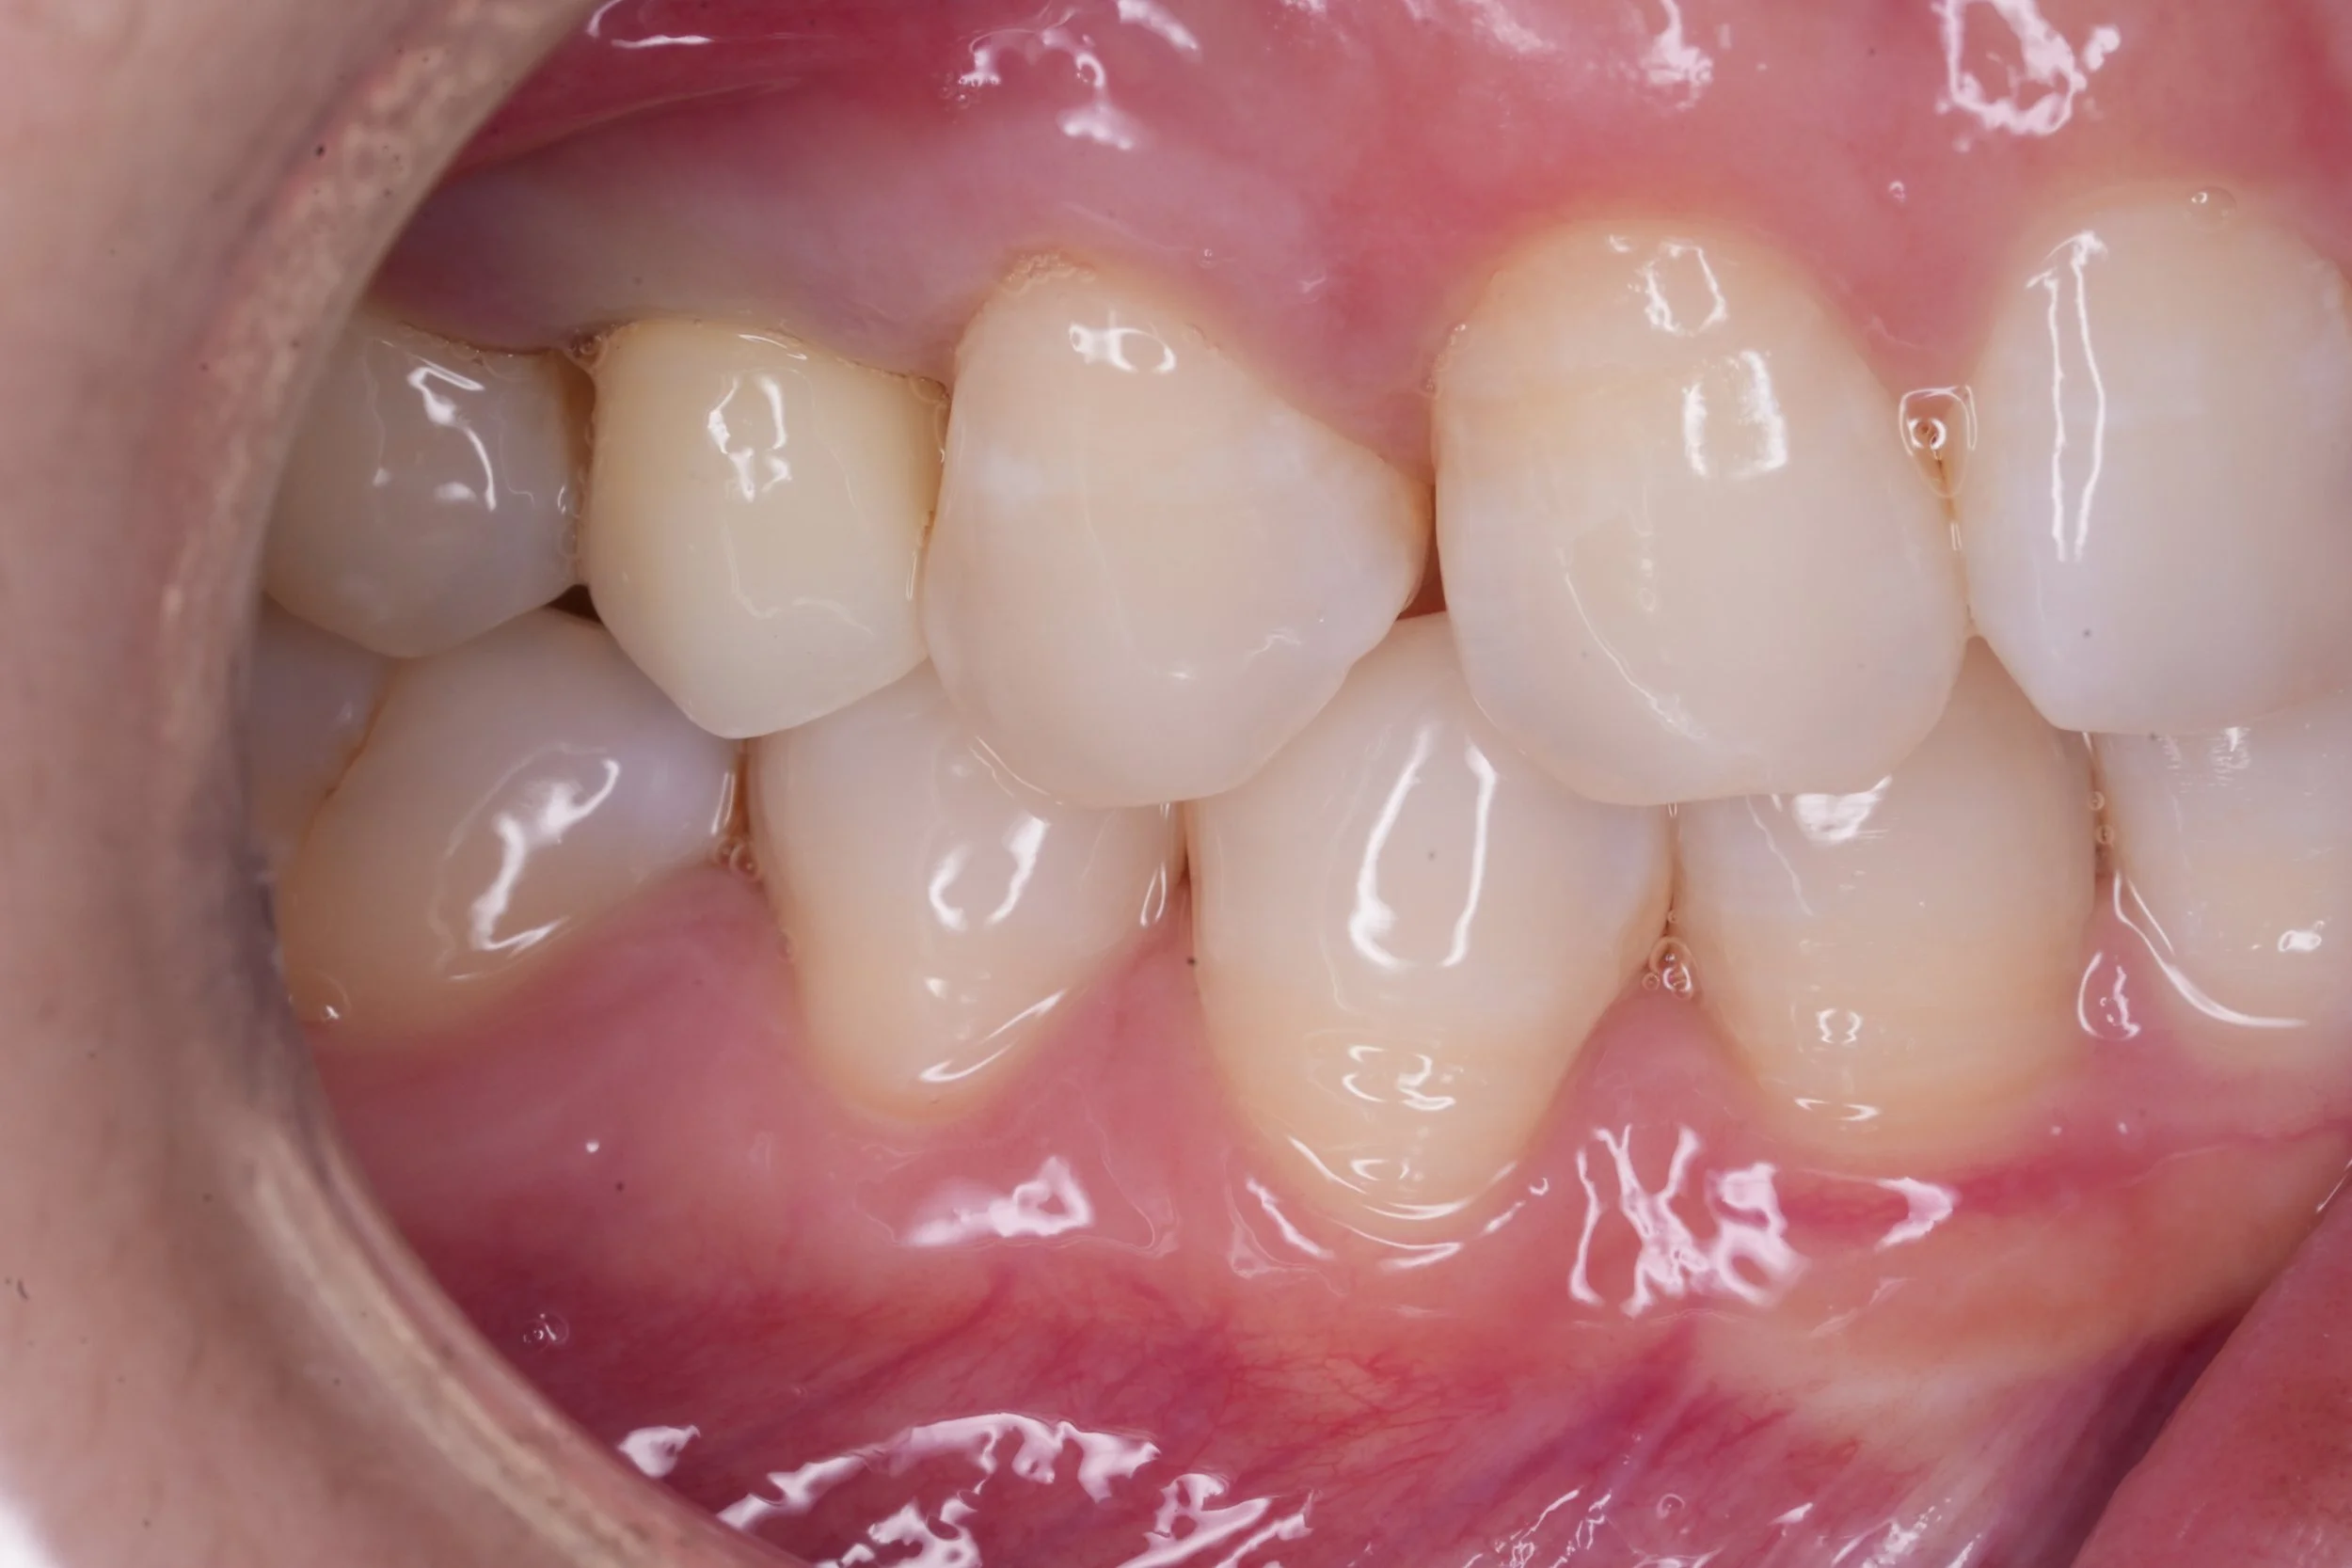

Fixed pros

Dental Implants